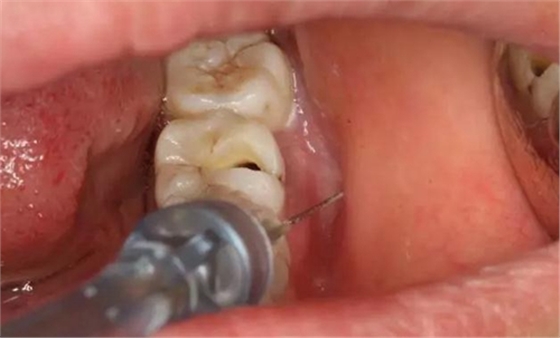

圖3. 取出棉球口內(nèi)發(fā)現(xiàn)37合面有開髓孔,探針出血,頰側(cè)牙齦紅腫。